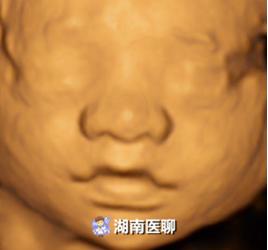

唇腭裂胎儿

正常胎儿